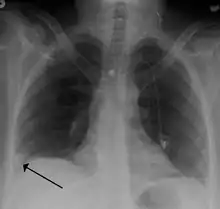

Рентгенографія органів грудної клітки

У більшості хворих із тромбоемболією легеневої артерії спостерігаються зміни на рентгенограмах грудної клітки, але у більшості випадків вони є неспецифічними. Проте цей метод діагностики залишається досить поширеним та доступним при підозрі на легеневу патологію. Найбільш поширеними рентгенографічними ознаками ТЕЛА є:

- Високе і малорухоме стояння куполу діафрагми в ділянці пошкодження легені.

- Збіднення легеневого малюнку (симптом Вестермарка) — ця ознака є більш специфічною, проте відносно рідкісною, спостерігається приблизно у 5 % хворих з ТЕЛА.

- Поява дископодібних ателектазів.

- Поява інфільтратів у легеневій тканині (більш характерно для інфаркт-пневмонії).

- Симптом Хемптона (трикутник Хемптона) — клиноподібне затемнення легеневого поля, основою повернене до плеври (найбільш характерна ознака ТЕЛА на рентгенографії грудної клітки).

- Розширення тіні верхньої порожнистої вени внаслідок підвищення тиску у правих відділах серця.

- Збільшення розмірів легеневої артерії — вибухання другої дуги (легеневого конуса) по лівому контуру тіні серця (ознака Фляйшнера).

- Кардіомегалія.[14]

- Поява рідини в плевральній порожнині.[11]

Зміни на рентгенограмі органів грудної клітки у більшості випадків не дозволяють поставити точний діагноз ТЕЛА, але може допомогти відрізнити інші захворювання, які мають подібні симптоми (крупозна пневмонія, пневмоторакс, плеврит, перикардит, аневризма аорти та інші).[9]